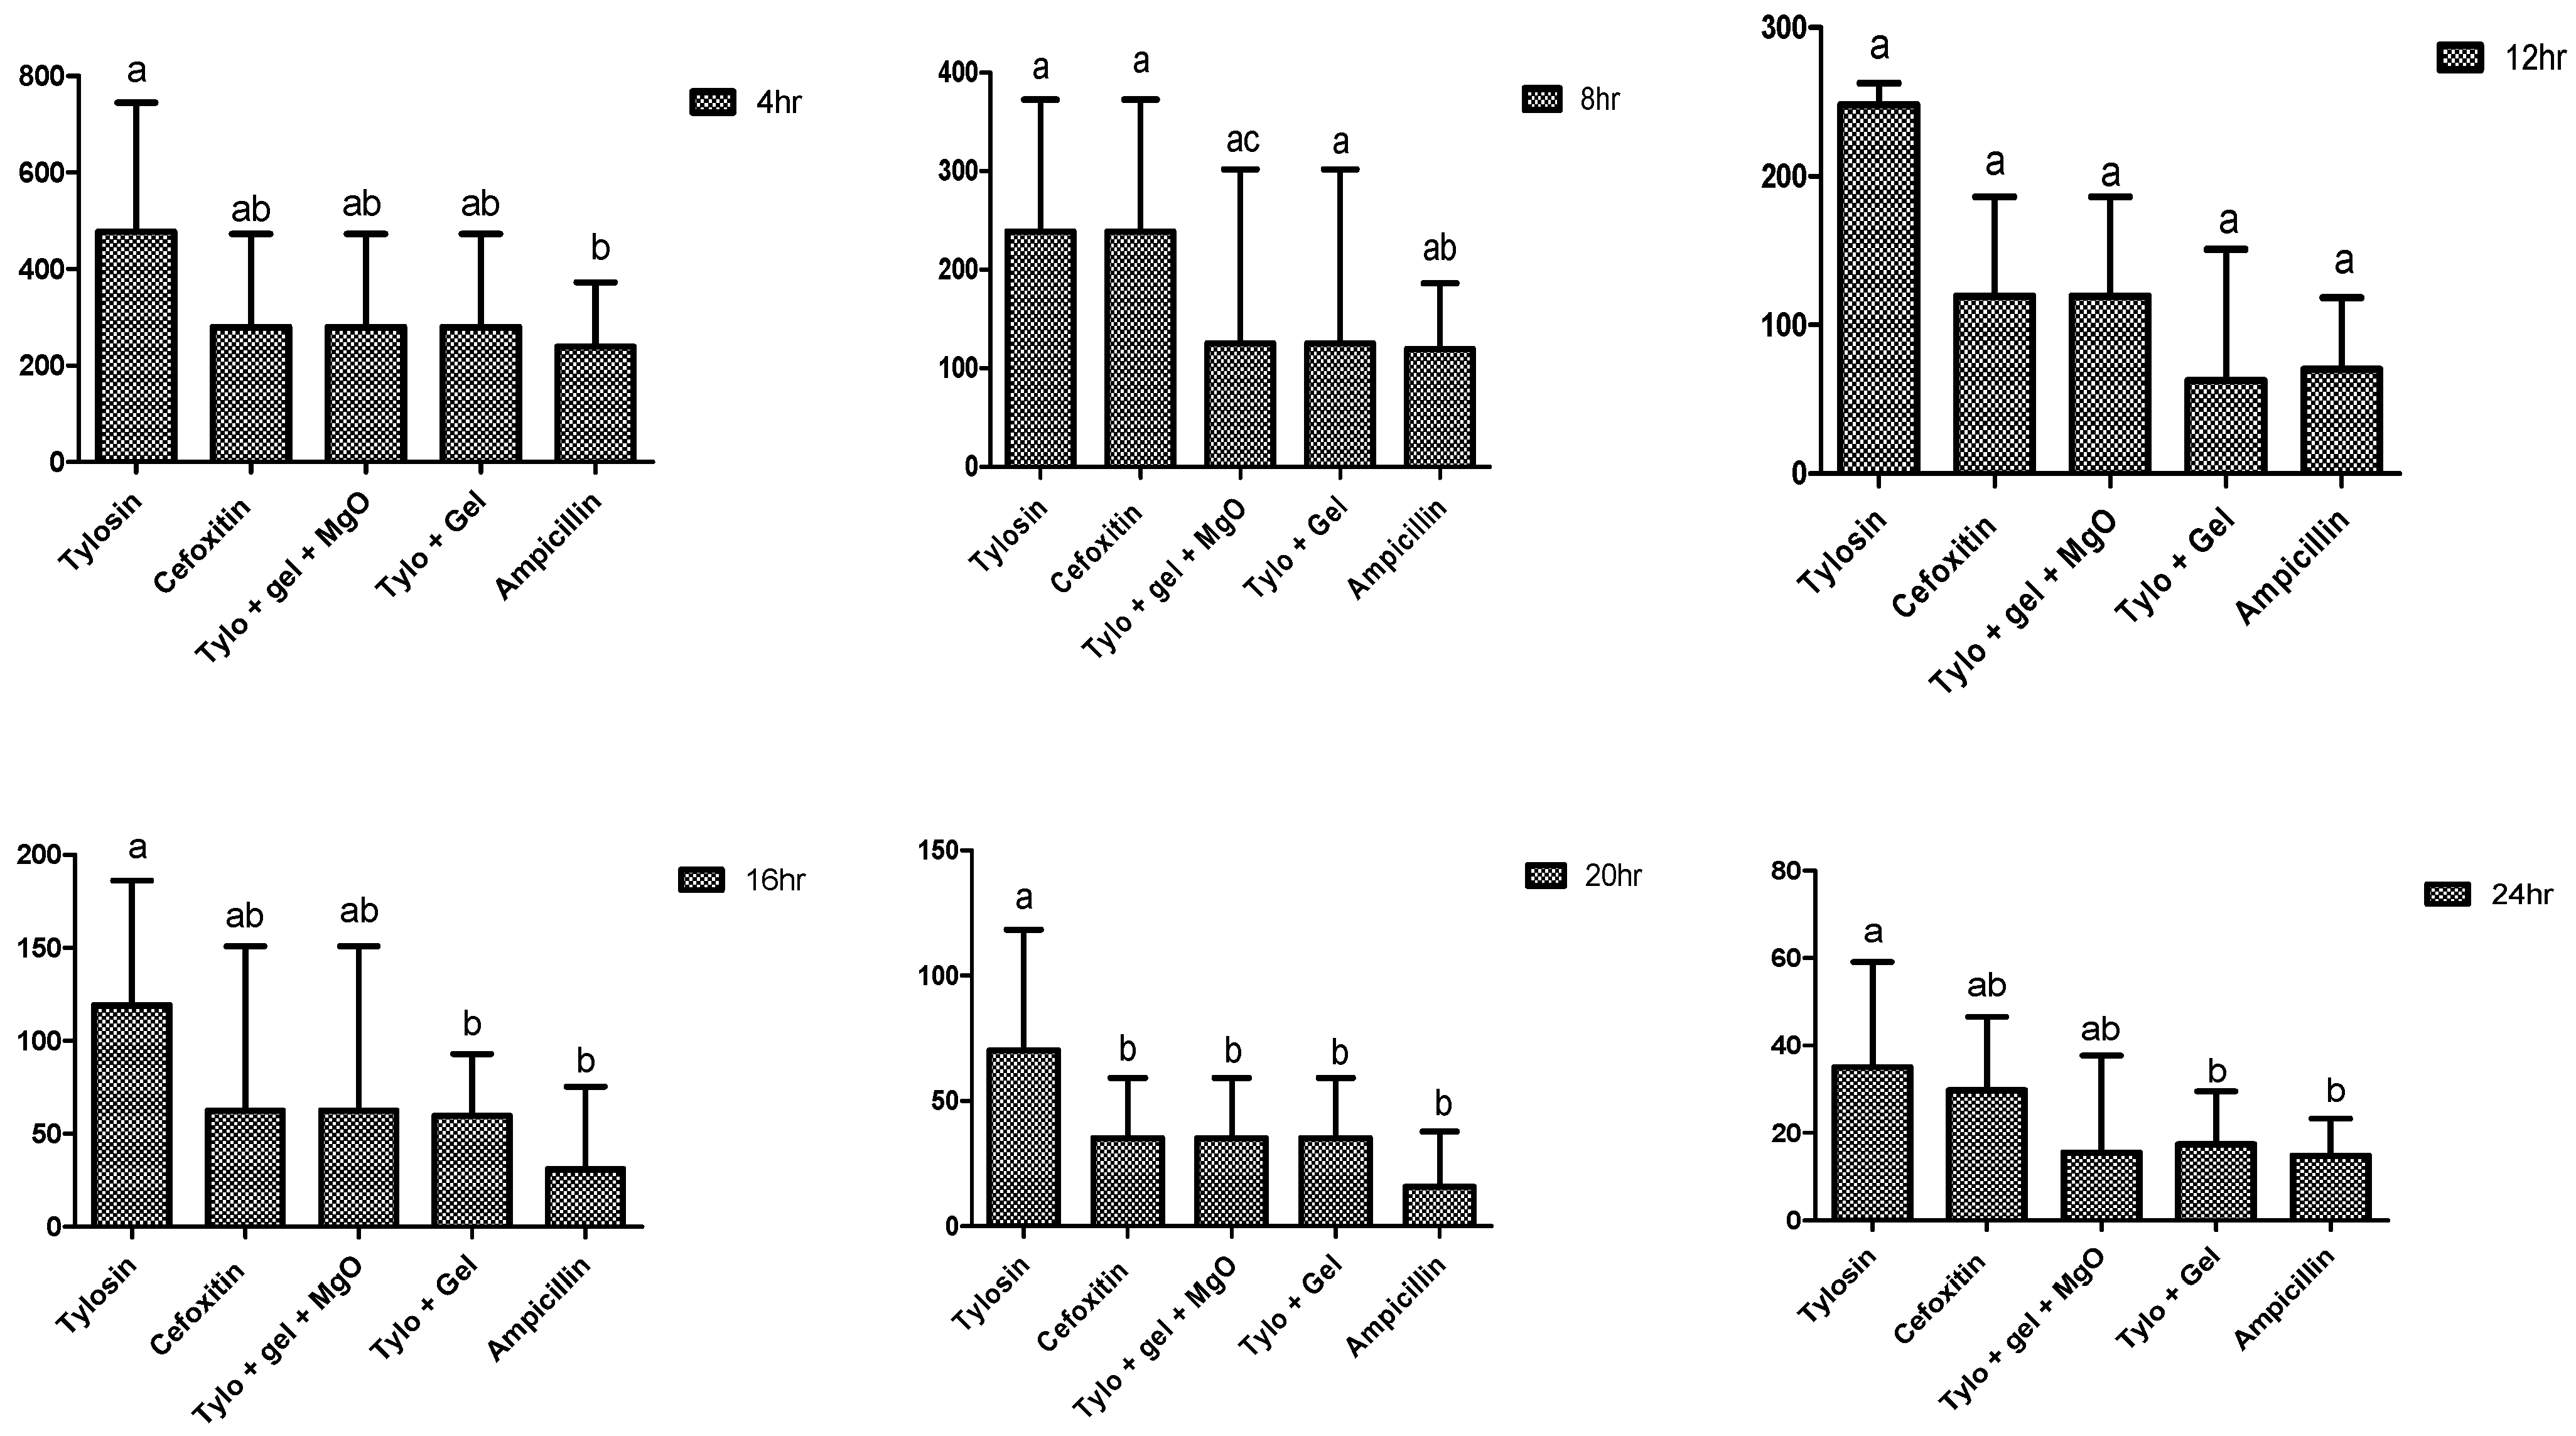

2.4. Antibacterial Potential of Gel-Based Nanoparticles and Antibiotics

4.7.1. Well Diffusion Assay

4.7.2. Minimum Inhibitory Concentration